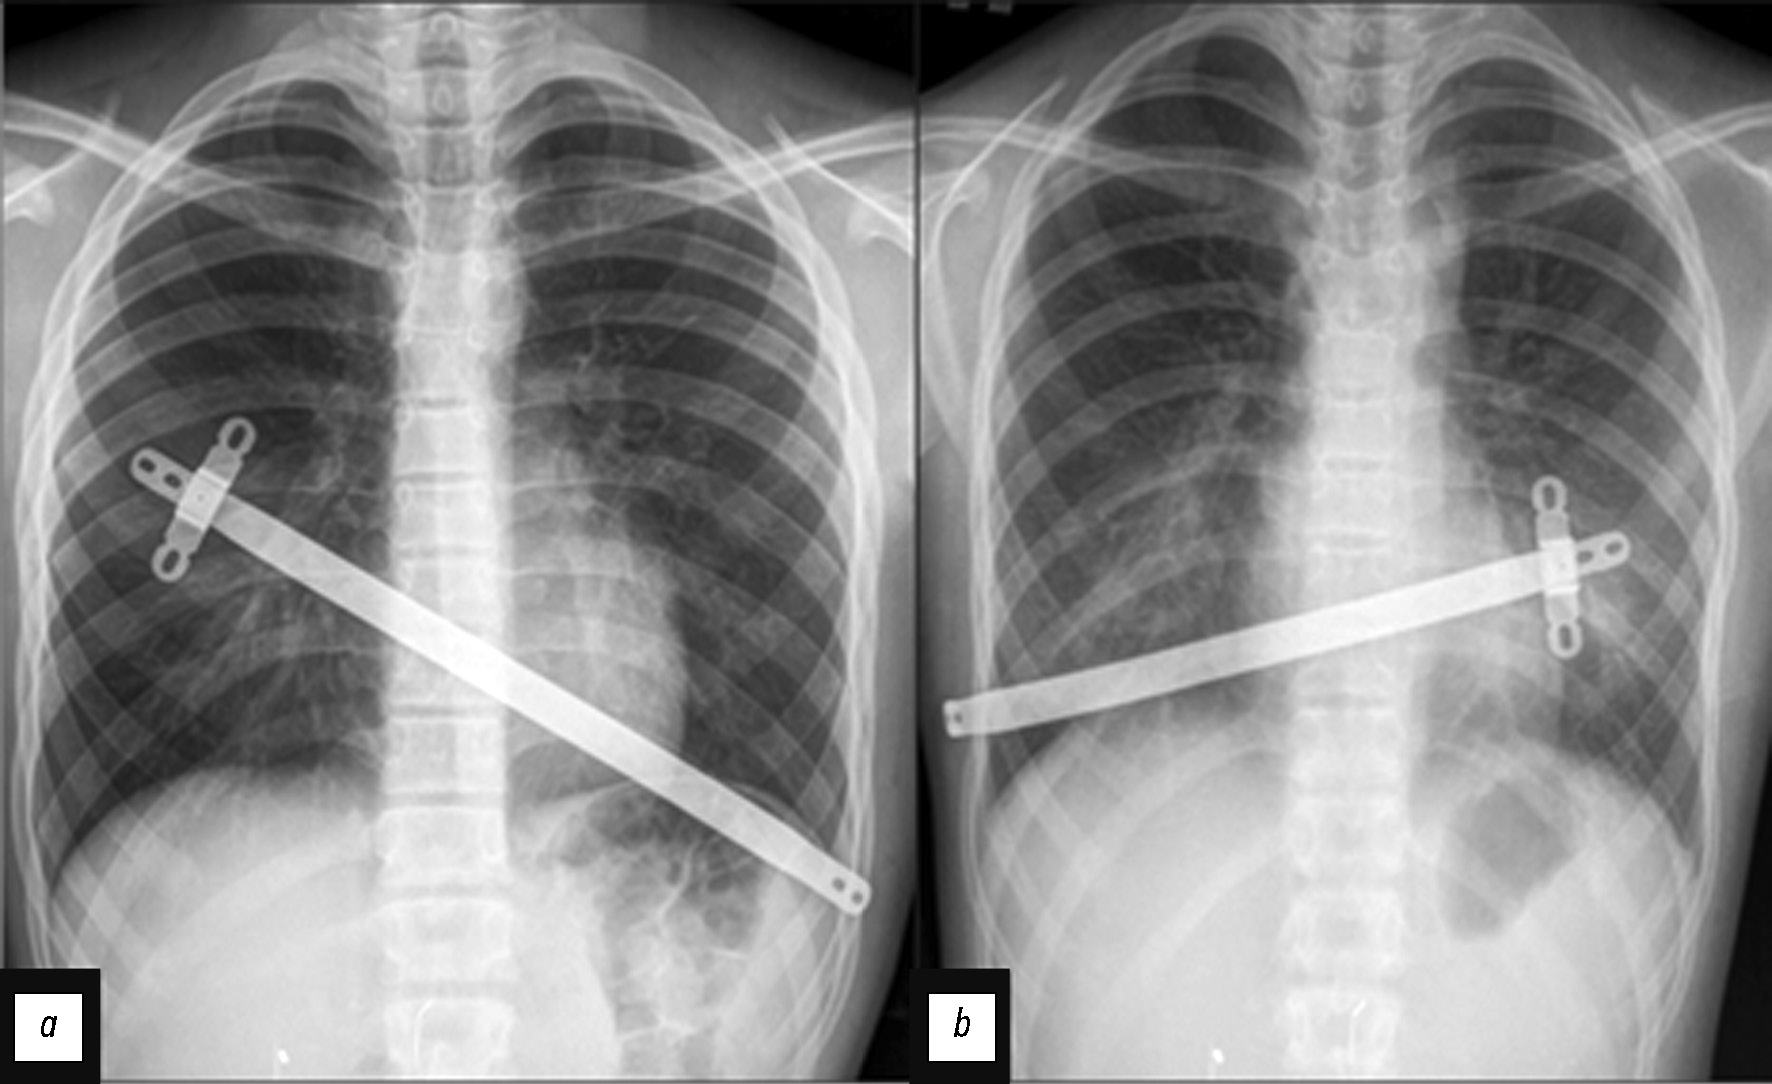

The sternal rotation angle is a crucial factor in planning the treatment strategy (Fig. 5).

Fig. 5. Chest magnetic resonance imaging at the level of maximum deformity; (a) the sternal angle rotation of 14.3°; (b) the sternal angle rotation of 31.1°.

An angle of ≥150° was considered significant for surgery and was reported in 44.7% of the total number of patients (Table 3). This position of the sternum required a unique oblique positioning of the sternal plate. The plate was positioned “toward” the acute sternal angle in preparation for subsequent rotation. Consequently, the sternal plate was transferred from the upper intercostal space on the right to the lower intercostal space on the left by traversing the apex of the deformity with sternal rotation when the acute angle expanded to the right (Fig. 6a). This occurred in 86% of all sternal rotation cases. In the case of the acute angle expanded to the left (14% of all cases), the sternal plate was accessed from the lower intercostal space on the right, through the apex of the deformity to the higher intercostal space on the left (Fig. 6b).